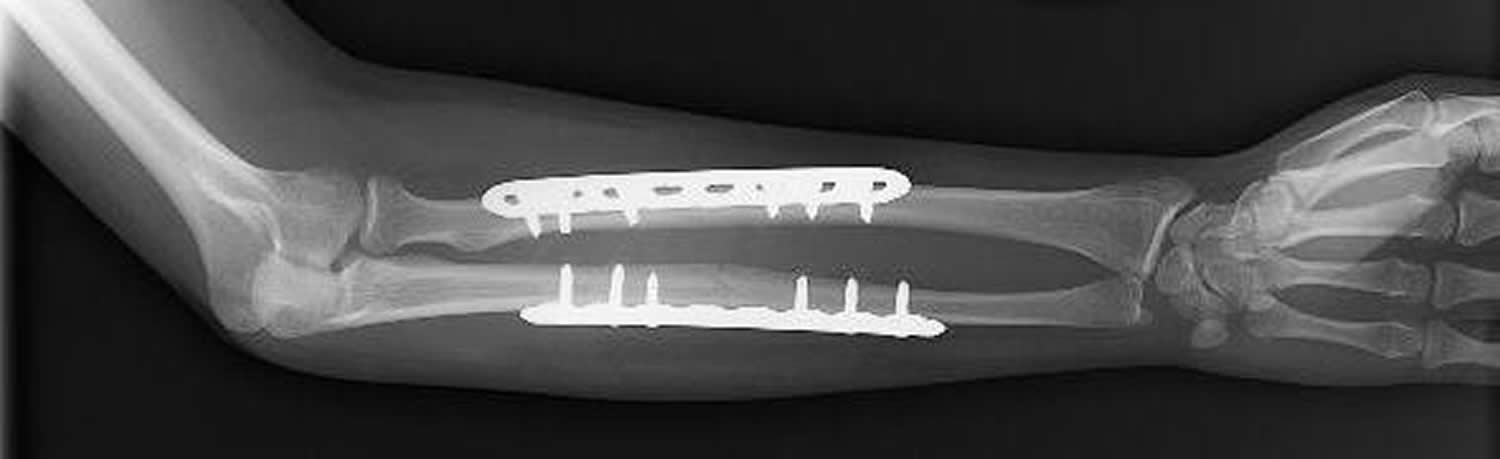

Медицинские снимки: Пластина в левом предплечье

Раздел: Альбом идей